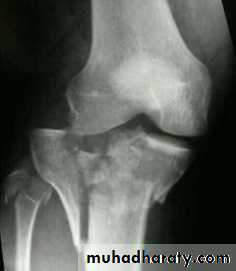

Tibial plateau fractures:Direct blow or fall from height may cause fracture of one tibial condyle or both. Fracture lateral condyle is the commonest named as bumper fracture caused by a force that abducts the tibia upon femur while the foot is fixed on ground. Patient usually is an adult, the knee joint is swollen, bruises, there is diffuse tenderness and doughy feel of haemarthrosis.ligaments injuries must be excluded.

Imaging : X-ray: anteroposterior, lateral & oblique

views. ct -Scan may used to detect amount of depression and comminuation.

Tibial plateau fracture